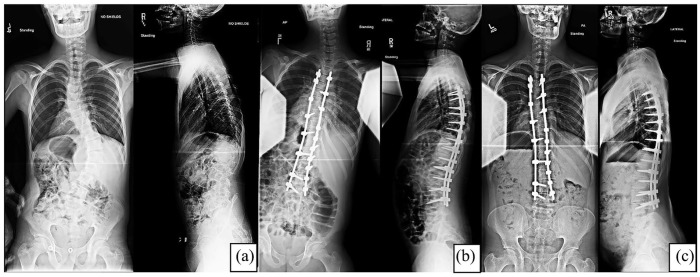

Methods: A retrospective review of 13 patients with Down syndrome who underwent surgical intervention for spinal deformity between 2000 and 2018 were identified. Postoperative complications were classified using the modified Clavien-Dindo-Sink system. Perioperative and final follow-up radiographic data were analyzed.

Results: The mean age at surgery was 14.2 years (11-19) with a mean follow-up of 3.6 years (0.4-6.2) at the time of data collection. Seven (54%) patients had postoperative complications, all related to wound healing. Three patients (23%) had major complications (Clavien-Dindo-Sink grade ≥3). These included one deep surgical site infection, one hematoma, and one seroma, all requiring surgical drainage. Four additional patients (31%) had minor complications (Clavien-Dindo-Sink grade ≤2).